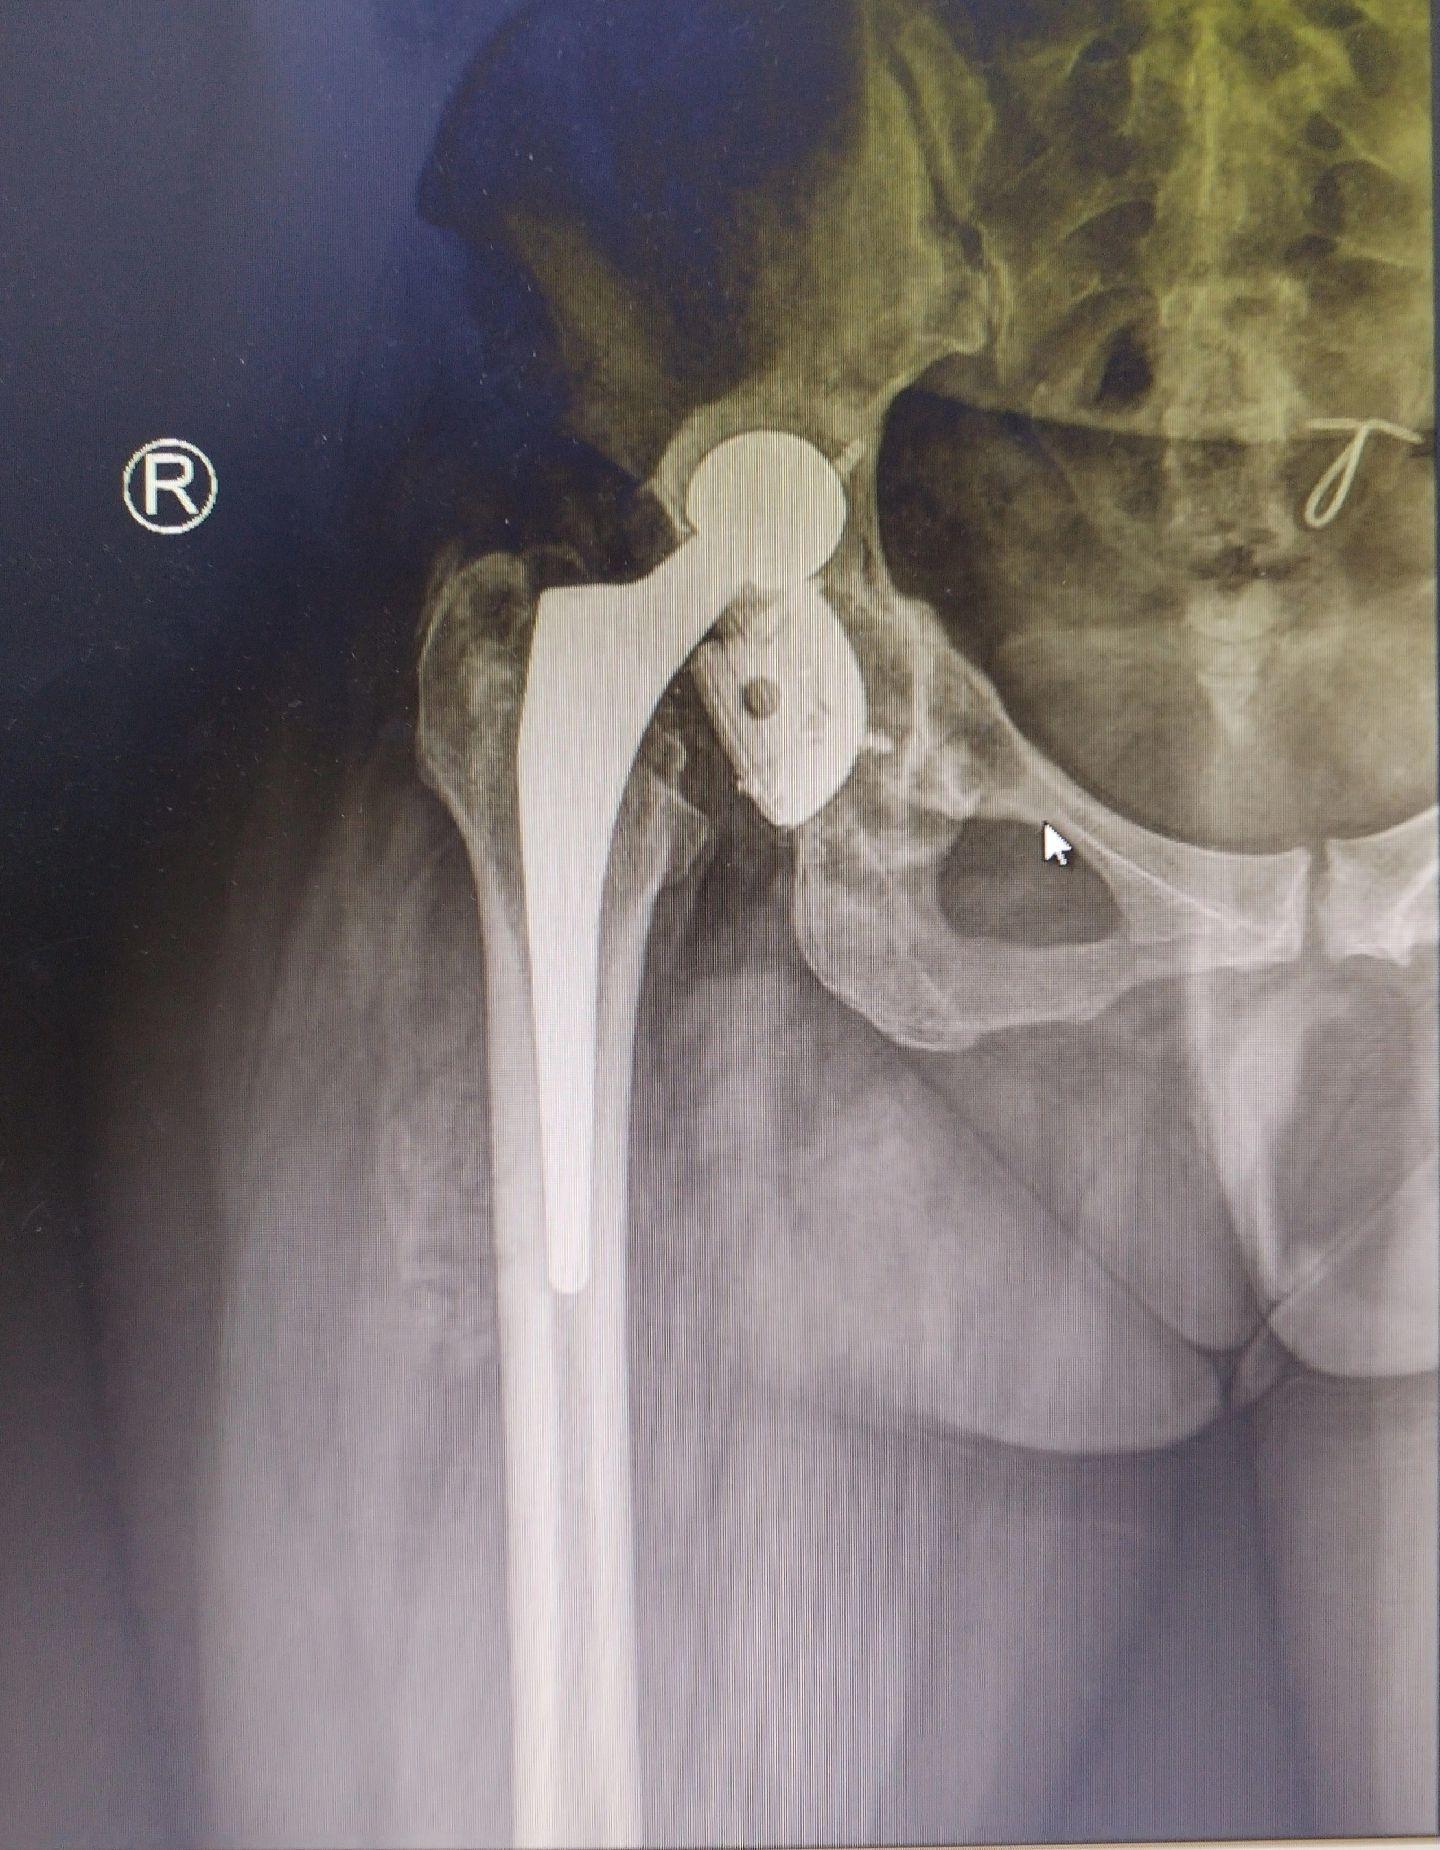

髋关节翻修术。髋关节置换术后假体磨损导致松动,一期翻修,只要重建的牢固,一样可以两天下床走路。愿每一个病人都能快速康复🌹关节置换

髋关节翻修术。髋关节置换术后假体磨损导致松动,一期翻修,只要重建的牢固,一样可以两天下床走路。愿每一个病人都能快速康复🌹